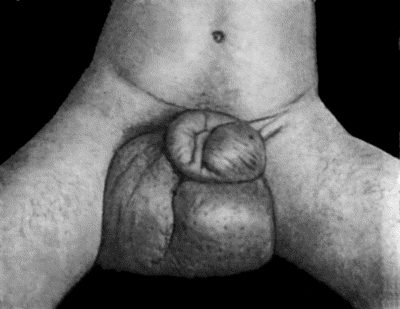

98.Elephantiasis of Penis and Scrotum 388

99.Multiple Sebaceous Cysts or Wens 390